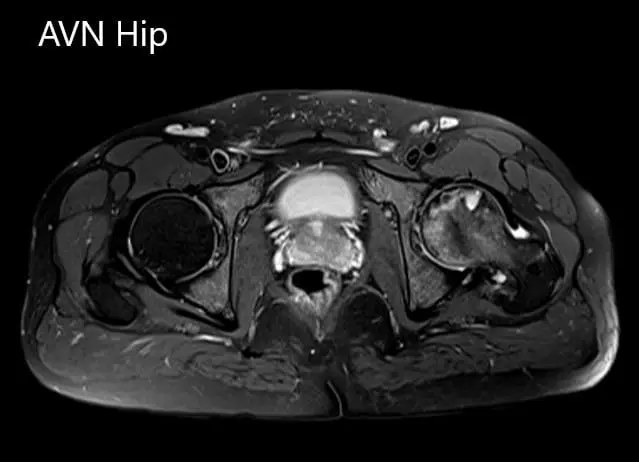

An MRI was obtained which suggested avascular necrosis of the left hip stage 3. There were altered signal intensity and bone marrow edema.

Axial sections of the T1WI and T2WI of MRI.